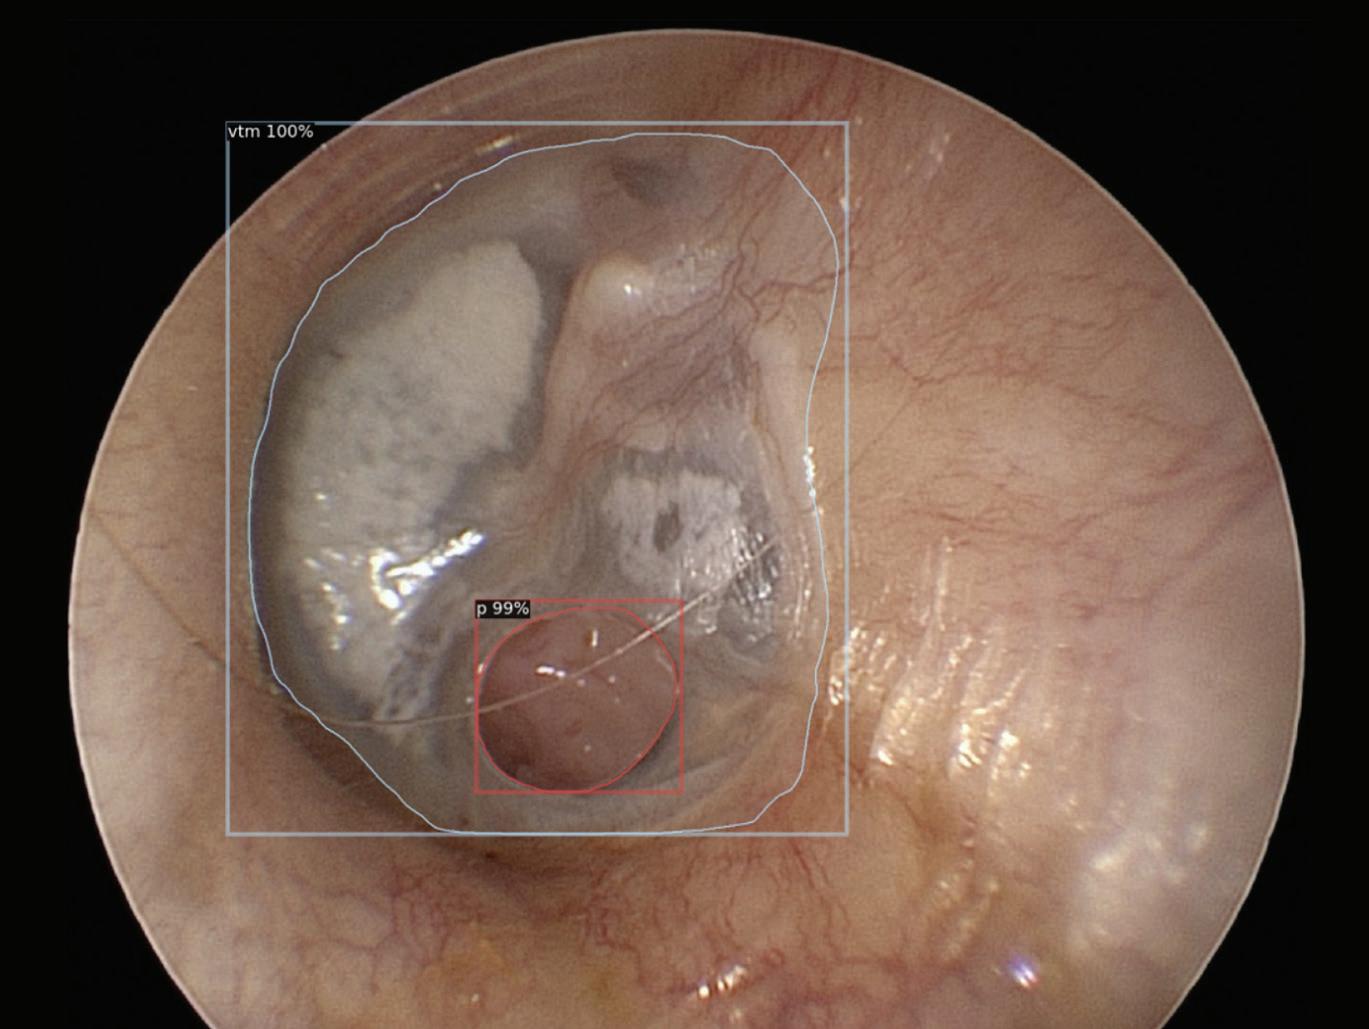

Together, Drs. Crowson and Nwosu identified areas within otology that could benefit from AI. Their work has concentrated heavily on automating otologic image interpretation using computer vision, a subfield of AI wherein computers are trained to analyze and extract meaningful information from visual data. Their first project in this space dealt with measuring tympanic membrane perforations.

of an automated ear drum perforation detection.

A tympanic membrane perforation, or a ruptured eardrum, will affect nearly six million individuals during their lifetime in the United States alone. Perforations in the tympanic membrane can negatively impact hearing and can be a predisposition to infections and the development of cholesteatoma.

The size of a perforation, or how much of the eardrum is missing, is one of many factors which inform the patient’s symptoms and necessary management. Conventionally, to determine the size of the hole in the eardrum, a provider makes a gross estimation through the visual inspection with the use of an otoscope, a practice prone to inaccuracy.

To find a solution for more accurate measurements, Drs. Nwosu and Crowson utilized an open-source deep learning architecture to train an instance segmentation model to segment and calculate the area of perforation. “These [instance segmentation] models allow a computer to learn boundaries of an object of interest within an image,” explained Dr. Nwosu. “We manually annotate the boundaries of objects of interest in highquality images and pass these images and annotations to the model to train on. The annotated images are like a blueprint, teaching the model the key features of each object.”

size,” said Dr. Crowson. “To our knowledge, this is the first study on this topic published in the literature, and we are especially excited and proud that the idea originated from one of our residents.”

After training their model, the duo tested the model on a separate set of images it hadn’t seen before to evaluate its ability to delineate the perforation's boundaries. The team then conducted an expert validation study comparing clinicians’ ability to estimate the size of a perforation against the computer's performance. On average, clinicians overestimated perforation size by 11 percent compared to the ground truth, while the model overestimated perforation size by only 0.8 percent. These findings were published in The Laryngoscope.

“We were pleased with these results, as it demonstrated the feasibility of a more accurate approach to a conventional practice, that computer vision can be used to estimate tympanic membrane perforation